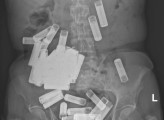

Μια ακτινογραφία έδειξε πως η πλειοψηφία των μπαταριών είχε συγκεντρωθεί στο στομάχι της, ευτυχώς χωρίς να φράξουν τον οισοφάγο. Για καλή της τύχη, καμία από τις μπαταρίες δεν έδειχνε σημάδια δομικής ζημιάς.

Η θεραπευτική ομάδα αρχικά ακολούθησε μια «συντηρητική» προσέγγιση, που σημαίνει ότι παρακολούθησε προσεκτικά την ασθενή για να δει αν και πόσες μπαταρίες θα περνούσαν από τον γαστρεντερικό σωλήνα μόνες τους.

Μέσα σε περίοδο μίας εβδομάδας, μόλις πέντε ΑΑ μπαταρίες είχαν περάσει από το γαστρεντερικό σύστημα.

Ακτινογραφίες που λήφθηκαν τις επόμενες τρεις εβδομάδες έδειχναν πως η πλειοψηφία των μπαταριών δεν είχαν περάσει στο έντερο. Σε αυτό το σημείο, η γυναίκα άρχισε να έχει έντονους κοιλιακούς πόνους.

Η χειρουργική ομάδα πραγματοποίησε μία λαπαροτομή για να έχει πρόσβαση στην κοιλιακή της χώρα και διαπίστωσαν πως το βάρος των μπαταριών είχε τεντώσει το στομάχι της το οποίο βρισκόταν πλέον πάνω από το ηβικό οστό. Κάνοντας μία μικρή τρύπα στο στομάχι, κατάφεραν να αφαιρέσουν 46 μπαταρίες.

Τέσσερις ακόμα μπαταρίες είχαν κολλήσει στο έντερο και αφαιρέθηκαν μέσω του πρωκτού. Το σύνολο των 55 μπαταριών είχε αφαιρεθεί και η γυναίκα ανέρρωσε χωρίς άλλες περιπέτειες.